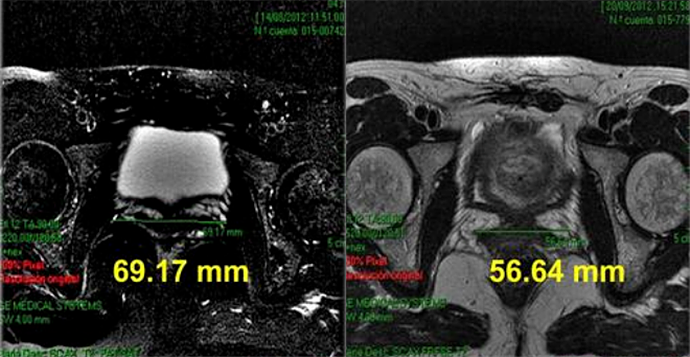

品牌方专门邀请了志愿者试用

试用后检测发现:

阴内壁组织明显厚实、紧致了!